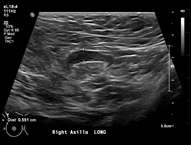

Features concerning for malignancy include round shape, increased cortical thickness and loss of fatty hilum1. The relationship of the lymph node cortex to hilum can be used to classify lymph node morphology and likelihood of malignancy. As the cortical thickness increases, there are reciprocal changes in the hilum beginning with hilar effacement and progressing to absence or replacement of the lymph node hilum2,3. Cortical thickening (figure 3) is considered the earliest morphologic change associated with malignancy; however, this finding is nonspecific with a low positive predictive value1-3. Absent/replaced hilum (figure 4) is the most specific for malignancy with a positive predictive value of 58-97%2.

Case: Axillary Lymphadenopathy  Figure 3

Figure 3. Right axillary lymph node with increased cortical thickness measuring 6 mm. Follow up ultrasound in 6 months recommended.